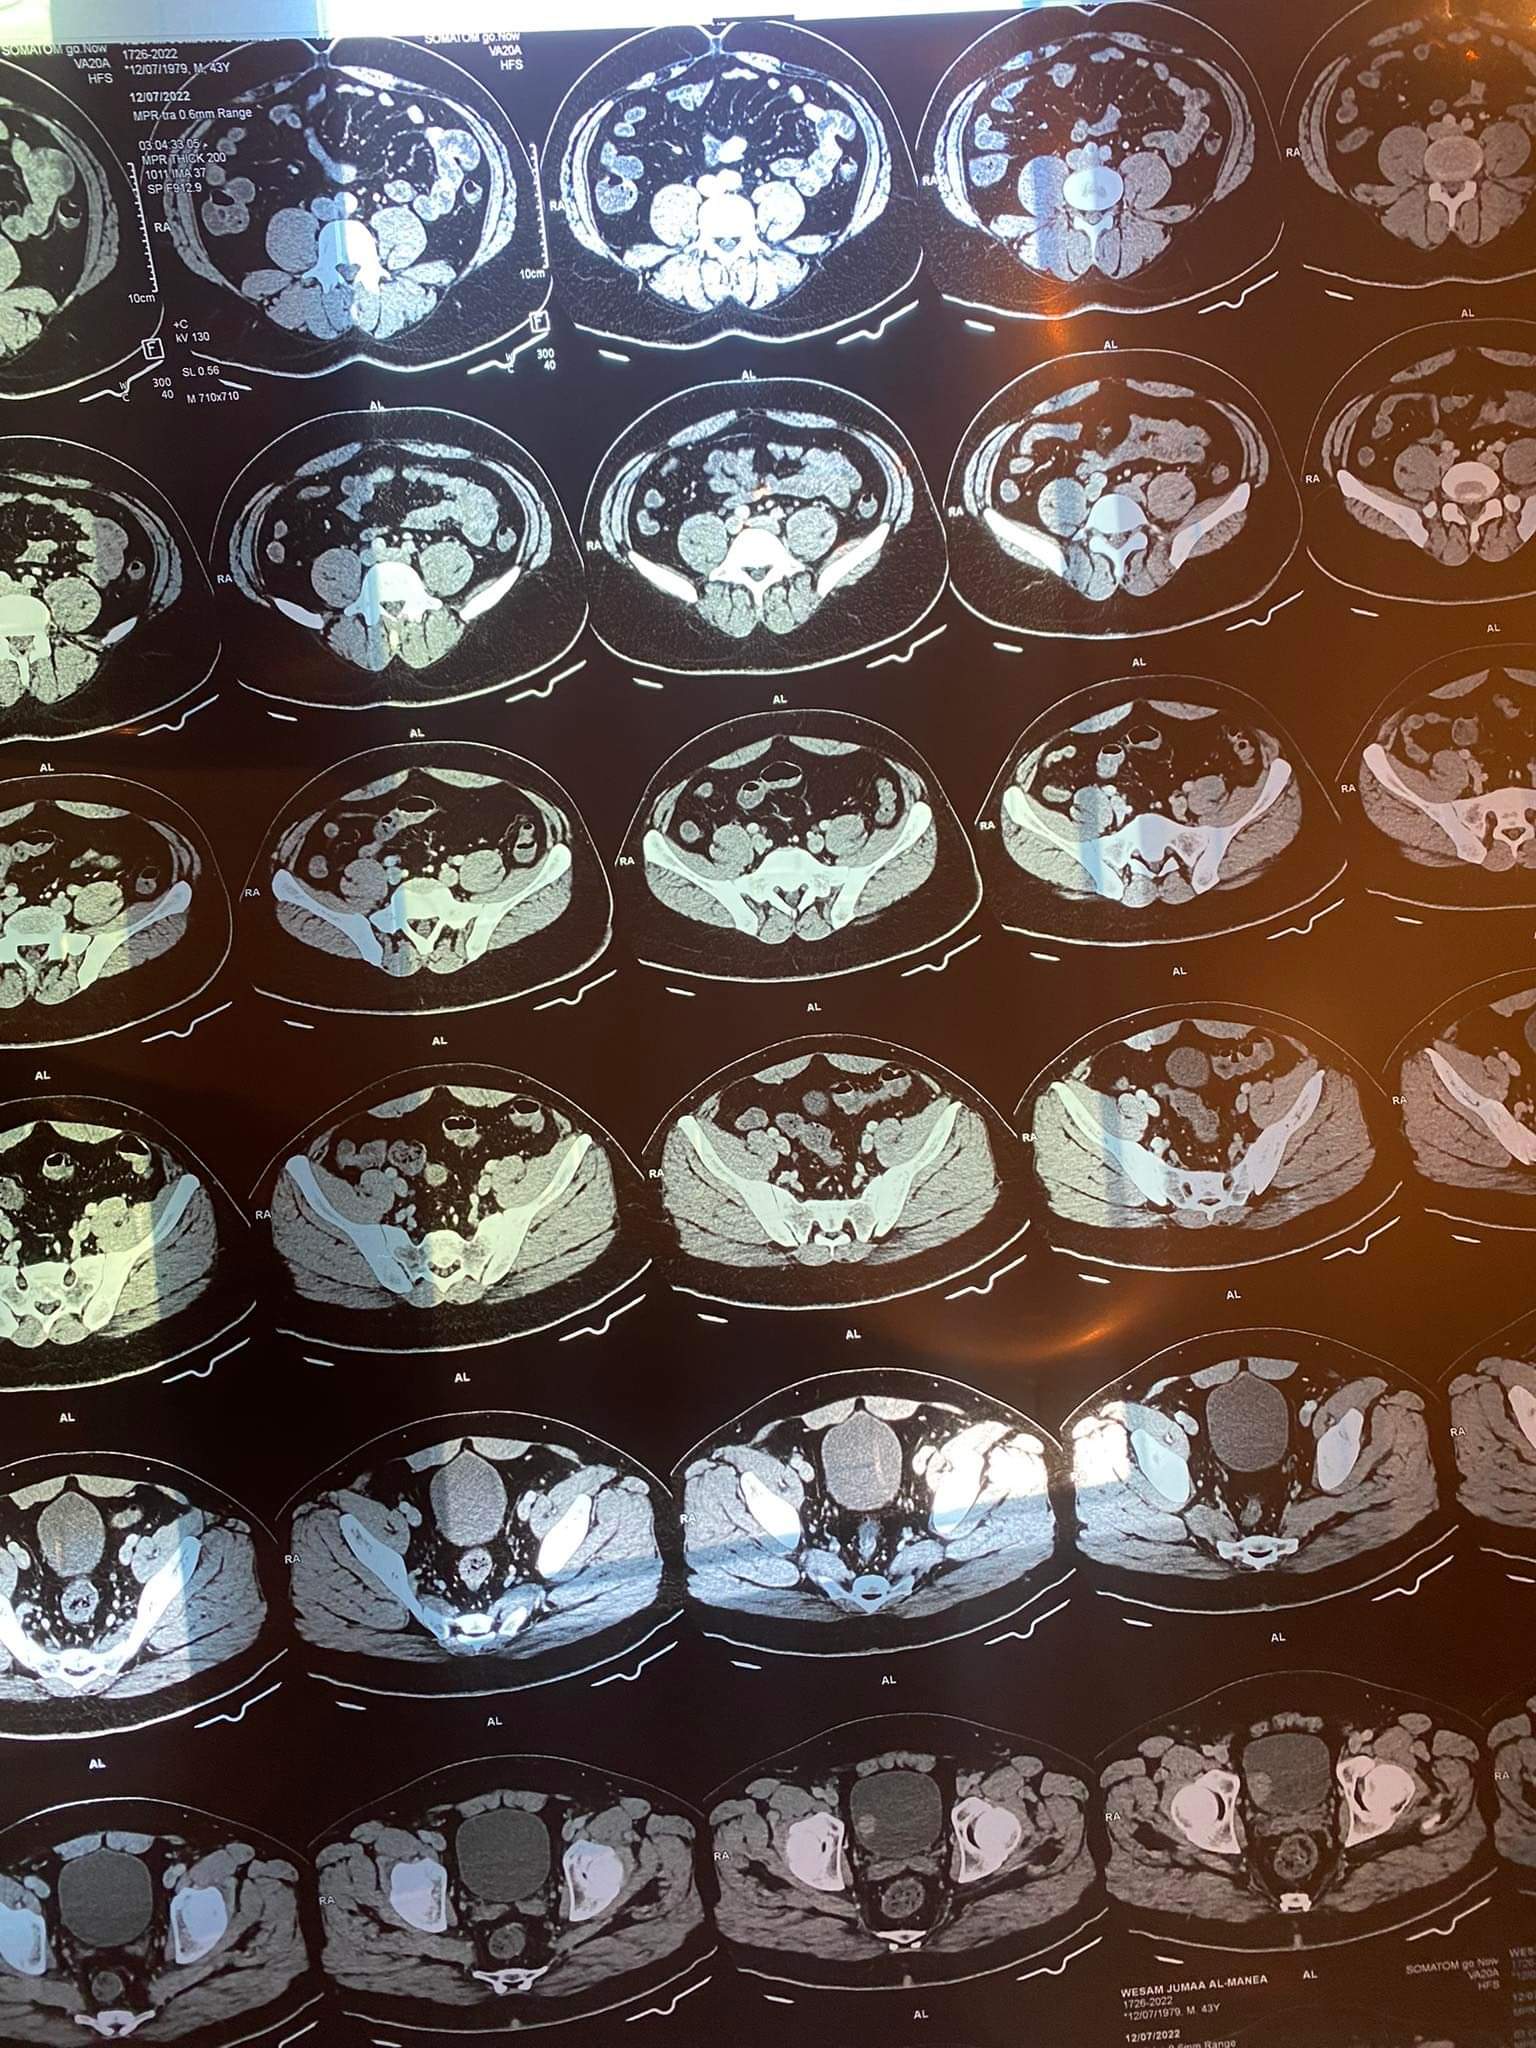

- يشير الفحص الطبي لديكم على وجود ورم في المثانة البولية بحجم 3 سم * 1.3 سم والذي يصل إلى كل الطبقات من المثانة البولية مع وجود عقد ليمفاوية .

- الكبد سليم وبحجم طبيعي .

- الكلى سليمة وبحجم طبيعي .

- الطحال سليم ولا يوجد أي بؤرات غير طبيعية .

- البنكرياس طبيعي وسليم .